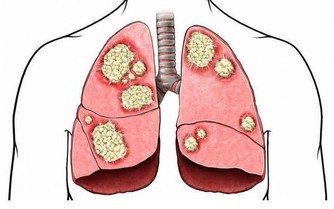

6.食物來不及消化,產生有毒物質誘發腸癌

晚餐吃得太晚,來不及完全消化,殘餘的蛋白質在腸道細菌的作用下會產生有毒的物質,又由於睡眠時腸道的蠕動很慢,使這些毒素在腸道內停留時間延長,在其長期刺激下,可誘發慢性腸炎及腸癌。